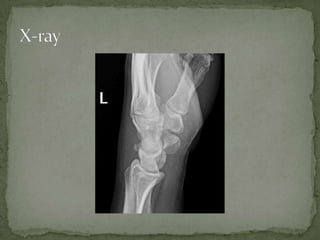

A 20-year-old male presented with left wrist pain after sliding head first into second base during a baseball game. On examination, there was swelling over the dorsal surface of the wrist with tenderness over the distal ulnar styloid process and limited range of motion due to pain. An x-ray revealed an avulsion fracture of the dorsal ridge of the triquetrum bone. The patient was prescribed pain medication, wrist splinting for 4-6 weeks, and a follow-up with orthopedic surgery.